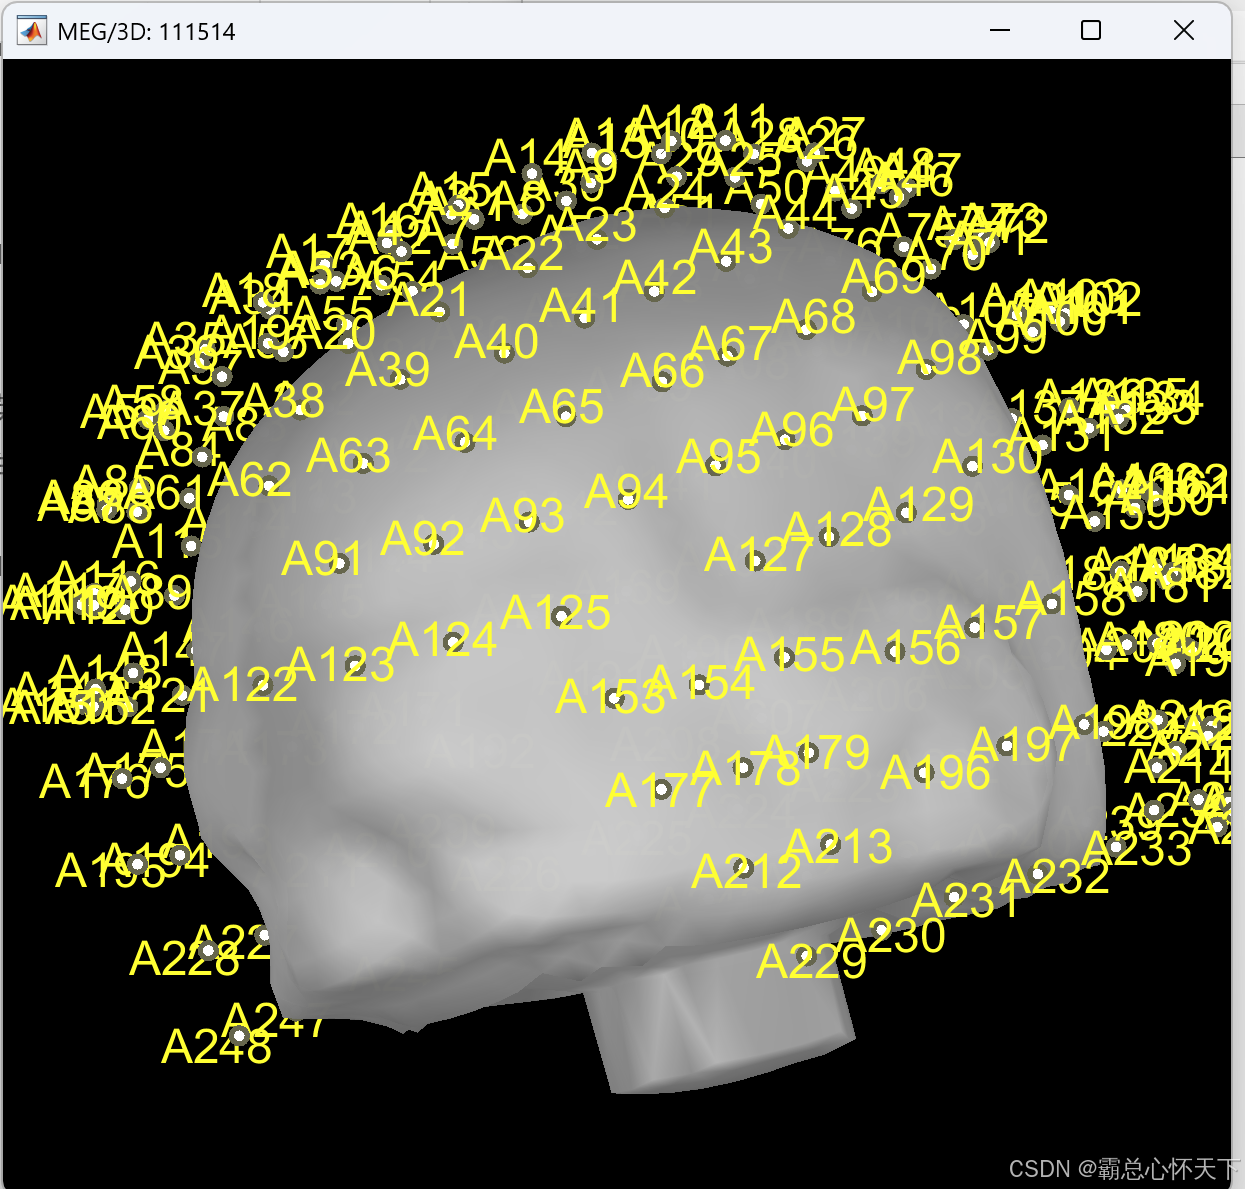

后会打开一个显示通道的页面

最上面一行的菜单,可以停留在图标上,会出现英文解释,自己看英文释义。根据上下左右前后移动外面的那个大黄罩子(大黄罩子相当于所有的通道点连接起来的曲面)

更改之后,不要忘记电极最上面那行图标中的OK,还可以查看电极位置,操作如下

这里是MEG和EEG另一个区别,这个区别也是我花了很长时间才搞清楚的。。。

但是MEG不一样,它的通道就是要悬浮着的,后来我去查了MEG的采集操作图片,确实,通道是不贴脑袋的

假如我这里理解的有误的话,请大家积极指正,以免误人子弟,目前为止我还是这样认为的